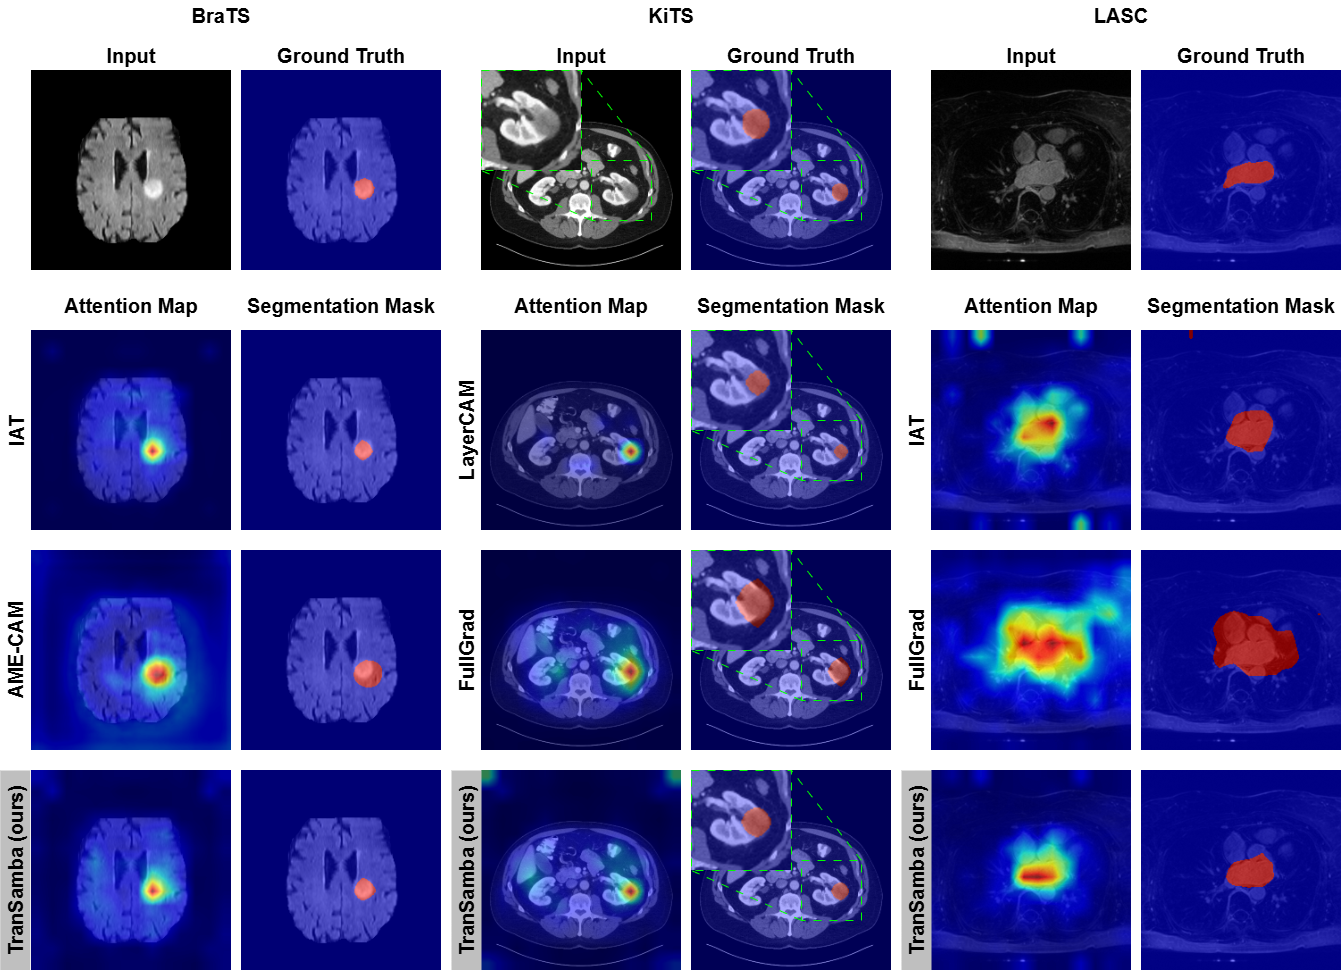

For each dataset, the qualitative results of the methods achieving the top-3 IoU are presented in \figurereffig4; a comprehensive qualitative comparison is provided in Appendix D. In the BraTS case, IAT and AME-CAM underestimate and overestimate the tumor area, respectively. In the KiTS case, FullGrad localizes a large area encompassing the tumor. Both LayerCAM and TranSamba pinpoint the small tumor, indicating their superiority in localizing small objects. In the LASC case, IAT attends to significant areas of the aorta and right ventricle, while FullGrad also includes a large area of the background in its segmentation. TranSamba attends to smaller areas of other substructures compared to IAT, resulting in a segmentation more conformal to the LA.

fig4